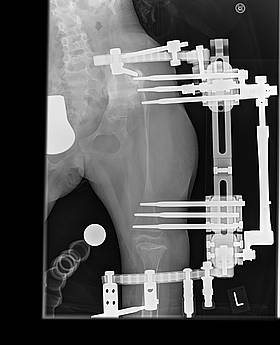

Sie bekommt auch einen externen Fixateur zum Verlängern des Oberschenkels. Dieser soll zunächst einmal die momentane Beinlängendifferenz ausgleichen. Diese Prozedur wird in den nächsten Jahren noch mehrmals wiederholt werden, der Oberschenkel soll überverlängert werden damit, wenn Lea ausgewachsen ist, eine Operation gemacht werden kann die sich "Pelvis support" nennt. Dabei wird der Überverlängerte Teil im oberen Bereich umgeklappt werden und somit eine bessere Stabilität für den Oberschenkel gewährleistet.

Die Anfangszeit der Verlängerung verlief einwandfrei. Wir konnten ohne Drehpause 3 1/2 Monate lang verlängern. Insgesamt schafften wir 8,3 / 8,4 cm Verlängerung. Das linke Bein war im Januar ein kleines Stückchen länger als das rechte Bein. Doch dann begann das Drama. Lea bekam eine eitrige Entzündung der Beckenpins nach der anderen. Der Knochen begann dünner zu werden. Die Beckenpins lockerten sich. Durch das lockern der Beckenpins, konnte sich der Oberschenkel ein kleines Stückchen ins Becken bohren. Im Juni kam dann die nächste OP. Leas 3 Beckenpins, die ständig eitrig entzündet waren und sich massiv gelockert hatten kamen raus und sie bekam etwas oberhalb am Becken zwei neue Pins eingesetzt. Danach ging es wieder bergauf. Der Knochen baute sich zwar nicht wieder auf, aber er baute sich auch nicht weiter ab. Der amerikanische Spezialist empfahl uns eine Zometa Therapie, sowie spezielle Vitaminpräperate aus Amerika zu nehmen.

Unsere Ärzte trauten sich aufgrund der dünne des Knochens und der vorangegangenen Komplikationen nicht an die Entfernung des Fixateurs, so dass eine erneute Operation duch den Amerikaner notwendig wurde. Er hat den externen Fixateur am 01.10.2012 operativ entfernt und stabilisierte den Oberschenkel mit einer speziellen Lochplatte. Im oberen Oberschenkelbereich fixierte er diese mit 5 Schrauben, im unteren Oberschenkelbereich mit 3 Schrauben. Lea darf nun insgesamt 7 Wochen nicht belasten. Nur Liegen und Sitzen.

Entfernen von Leas Fixateur